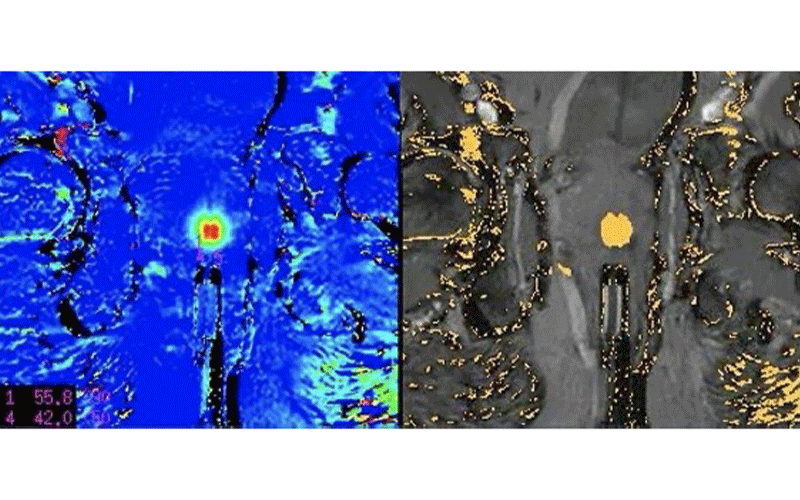

In the MRI-guided laser focal therapy technique, the tip of the laser is heated to approximately 60 degrees Celsius to destroy the cancer along with a 1-centimeter margin of normal tissue around the tumor. MR thermometry provides real-time temperature feedback to ensure accurate delivery of treatment without harming adjacent structures.

“With MRI, we can see where important anatomic structures are located like the rectal wall, the neurovascular bundles that control erectile function, and the little muscle that keeps someone continent,” said Dr. Feller, who is also a member of RSNA’s Public Information Advisors Network. “Because we can see those structures, we can put a safety cursor on them that will shut the laser off if they start to heat up. As a result, the procedure is both very safe and precise.”